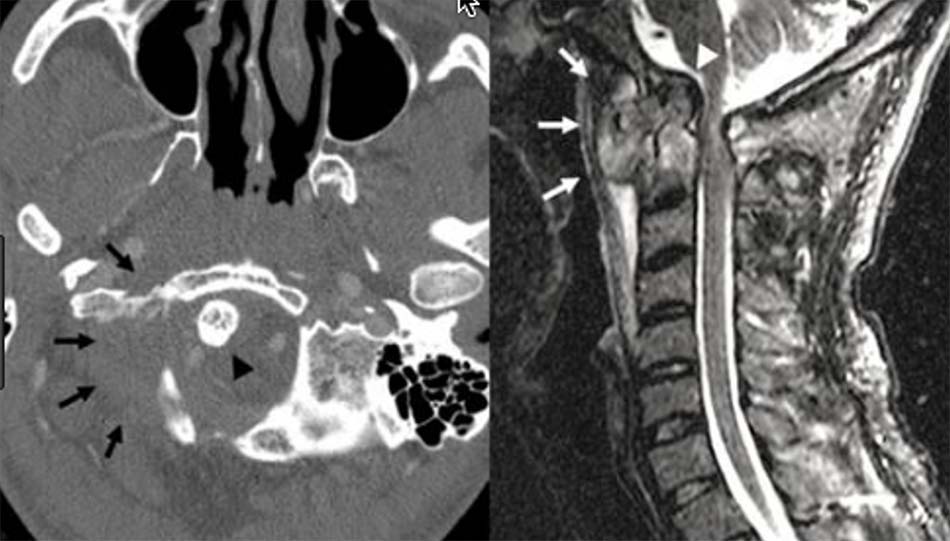

2.4.1. Tật lồng đáy sọ

Tật lồng đáy sọ là bất thường vùng cổ chẩm có nguy cơ gây tử vong cao do mất vững đội – trục và có thể gây trật đội – trục khi chỉ gặp chấn thương nhỏ. Điều trị phẫu thuật gặp nhiều khó khăn. Nhiều quan điểm cho rằng chèn ép thân não phía trước nên được giải ép bằng đường mổ lối trước qua khoang miệng và sau đó nẹp cổ chẩm. Trong dị dạng Chiari, có thể phẫu thuật giải ép mai chẩm và cố định cổ chẩm [4]. Phương pháp khác đã được áp dụng khi phẫu thuật can thiệp làm giãn khớp đội – trục và vít khối bên [2]. Một nghiên cứu tiến hành trên 190 bệnh nhân tật lồng đáy sọ do Goel và cộng sự tiến hành nhằm đánh giá sự thích hợp trong phương pháp phẫu thuật. Dựa vào sự kết hợp với dị dạng Chiari, tật lồng đáy sọ được chia vào 2 nhóm bao gồm không có sự kết hợp với dị dạng Chiari hoặc có Chiari. Với những bệnh nhân tật lồng đáy sọ không có Chiari kèm theo thích hợp hơn khi được phẫu thuật giải ép đường miệng và nếu có Chiari kèm theo thì phải giải ép lỗ chẩm. Sau phẫu thuật giải ép lối trước ở những bệnh nhân không có Chiari nên được cố định cổ chẩm tuy nhiên tỷ lệ cố định cổ chẩm ở nhóm giải ép lỗ chẩm trong Chiari hạn chế hơn [3].

Chẩn đoán Tật lồng đáy sọ được xác định trên chẩn đoán hình ảnh [1], có 3 đường cơ bản được xác định trên phim chụp nghiêng và đường trên phim chụp thẳng như sau:

- Đường Chamberlain: nối từ bờ dưới lỗ chẩm tới bờ dưới khẩu cái cứng. Triệu chứng lâm sàng xuất hiện khi đỉnh mỏm nha nằm phía trên đường kẻ này. Tuy nhiên điều bất lợi khi xác định đường Chamberlain do bờ dưới lỗ chẩm khó xác định trên phim nghiêng.

- Đường McGregor: nối từ điểm thấp nhất của vòng cung chẩm tới bờ trên thành sau khẩu cái cứng, nếu đỉnh mỏm nha nằm trên đường này 4,5 mm, có sự bất thường.

- Đường Mc Rae: bản chất là đường kính lỗ chẩm, đường nối từ bờ trước đến bờ sau lỗ chẩm. Không có triệu chứng lâm sàng nếu đỉnh mỏm nha nằm dưới đường này.

![Tật lồng đáy sọ trên cắt lớp vi tính và cộng hưởng từ [1]](https://chanthuongvacotsong.bachmai.gov.vn/wp-content/uploads/2021/01/tat_long_day_so.jpg)

Đường Fischgold and Metzger: xác định trên phim thẳng trước sau là đường thẳng nối 2 điểm giữa chân mỏm chũm và nền sọ, bình thường đường này nằm phía trên đỉnh mỏm nha 10,7 mm và trên khớp đội chẩm 11,6 mm. Nếu khoảng cách này ngắn lại chẩn đoán xác định dị dạng lồng đáy sọ.